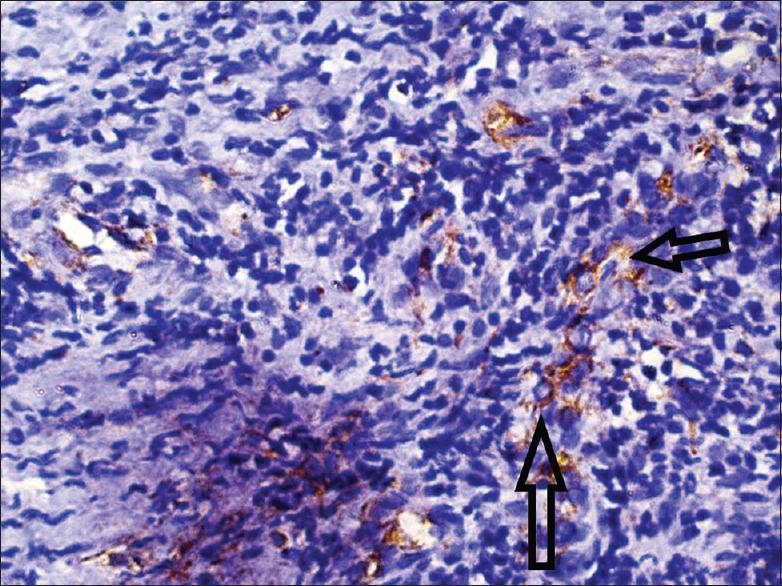

Necrotizing ulcerative periodontitis (NUP) is a painful and debilitating condition seen mostly in an immunocompromised state. Although squamous cell carcinoma (SCC) on gingiva is not uncommon, its presentation as a benign necrotizing lesion on gingiva is rare. Such presentations may lead to delayed diagnosis and poor prognosis. This report describes a case of a 34-year-old male presenting clinically with NUP around mandibular posterior teeth. Clinical features were misleading, but the histological findings established the diagnosis of well-differentiated SCC. Immunohistochemistry also showed features of epithelial-mesenchymal transition with decreased expression of E-cadherin and increased vimentin expression showing local invasion and metastasis. The patient was referred to the oncology department for evaluation of possible metastasis and further management of carcinoma.

坏死性溃疡性牙周炎(NUP)是一种主要见于免疫功能低下状态的疼痛性且使人衰弱的病症。虽然牙龈鳞状细胞癌(SCC)并不罕见,但其表现为牙龈上的良性坏死性病变则较为罕见。此类表现可能导致诊断延迟和预后不良。本报告描述了一例34岁男性患者,临床上表现为下颌后牙周围的NUP。临床特征具有误导性,但组织学检查结果确诊为高分化SCC。免疫组织化学还显示出上皮-间质转化的特征,E-钙黏蛋白表达降低,波形蛋白表达增加,提示局部侵袭和转移。该患者被转诊至肿瘤科,以评估可能的转移情况并对癌症进行进一步治疗。